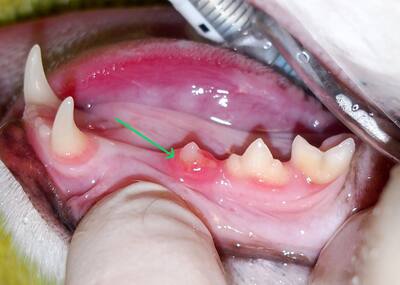

1. Absorción dental en un gato

Aunque los gatos no desarrollan caries en sí mismas, podríamos comparar un poco la absorción dental felina con una caries en humanos, porque incluso si las dos condiciones son muy diferentes, en ambos casos, habrá un agujero en el diente. En los gatos, este agujero en el diente proviene de la absorción del diente en sí. De hecho, es una destrucción de tejido progresivo del diente, y esto desafortunadamente puede suceder en varios dientes. El diente afectado parece desprecio y la encía alrededor proliferará y cubrirá el diente para proteger la lesión. Estas son lesiones dolorosas para el gato, aunque este último manifiesta muy pocos síntomas, de ahí la importancia de consultar a su médico veterinario. En la imagen de arriba, en realidad podemos ver la parte roja, roja y cubierta del premolar un poco como la nieve puede cubrir una superficie después de la tormenta.